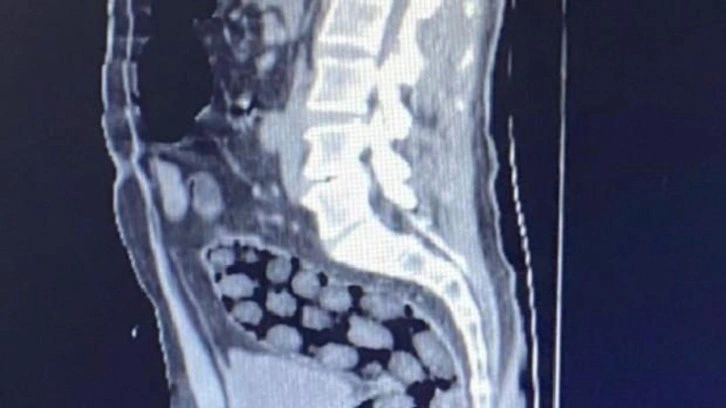

Açıklamada, “Bitlis Emniyet Müdürlüğü Narkotik Suçlarla Mücadele Şube Müdürlüğü ve İstihbarat Şube Müdürlüğü ekiplerince gözaltına alınan ve Tatvan Devlet Hastanesine sevk edilen şüphelilerin röntgen ve tomografi görüntülerinde mide ile bağırsaklarında çok sayıda yabancı cisim bulunduğu tespit edilmiş, yapılan tıbbi müdahale ile şüphelilerin paketleyerek yuttuğu toplam 91 adet daralı ağırlığı 1 kilo 126 gram metamfetamin maddesine el konulmuştur. Şüpheliler, çıkarıldığı adli mercilerce tutuklanarak cezaevine gönderilmiştir. Hemşehrilerimizin huzuru ve güvenliği için uyuşturucu madde imalatı, kaçakçılığı ve kullanımına karşı yürütülen kararlı mücadelemiz devam edecektir” denildi.